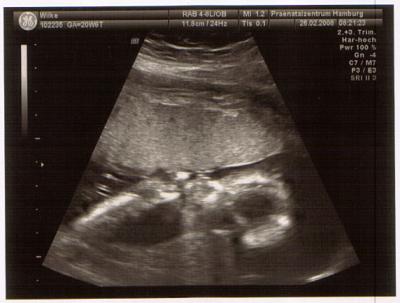

Und hier noch einmal als Daumenlutscher :o)